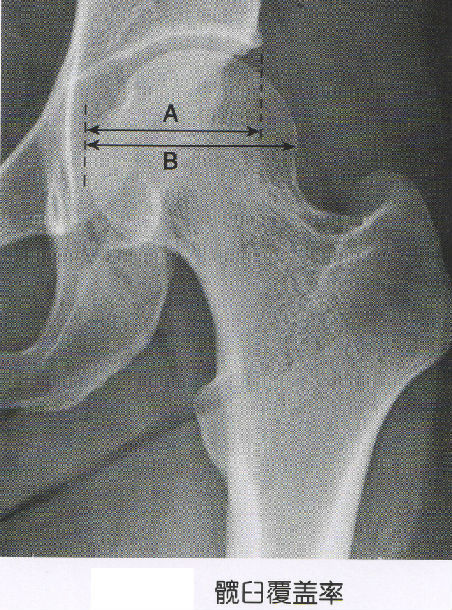

的分级方法是依据股骨头相对于髋臼的脱位程度而定,最常用的crowe法

Ⅱ型:不全脱位50%-75%;Ⅰ型:不全脱位 50%;crowe于1979年提出的分型